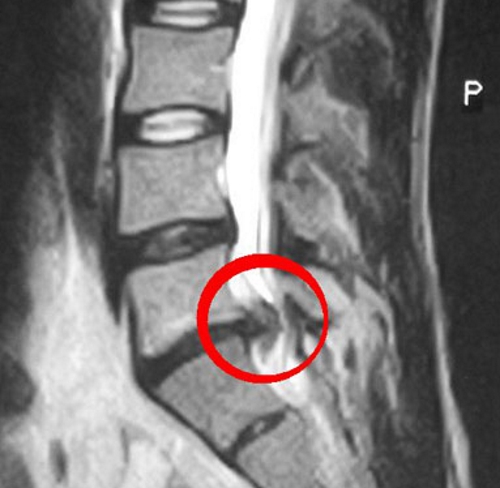

Протрузия диска — это выпячивание межпозвоночного диска за пределы позвоночника. Фиброзные кольца сохраняют прочность лишь до определенного предела. При их износе диск начинает деформироваться и выпячиваться. Если фиброзное кольцо остается целым или выпячивается не более чем на 6 мм, ставится диагноз «протрузия». В этом случае ядро остается в пределах кольца.

Протрузия опасна тем, что может перейти в грыжу. При образовании межпозвоночной грыжи фиброзное кольцо может повреждаться или разрываться под давлением. В некоторых случаях ядро смещается в спинномозговое отверстие, что приводит к защемлению нерва в спинном мозге.

При протрузии выпячивание составляет до 5 мм, и фиброзное кольцо не повреждено. В случае грыжи наблюдается разрыв кольца с выпячиванием более 6 мм. Симптоматика обоих состояний очень схожа.

Протрузия – выпячивание от 1 до 3 мм. Пролапс – выпячивание от 3 до 6 мм. Грыжа – выпячивание более 6 мм.